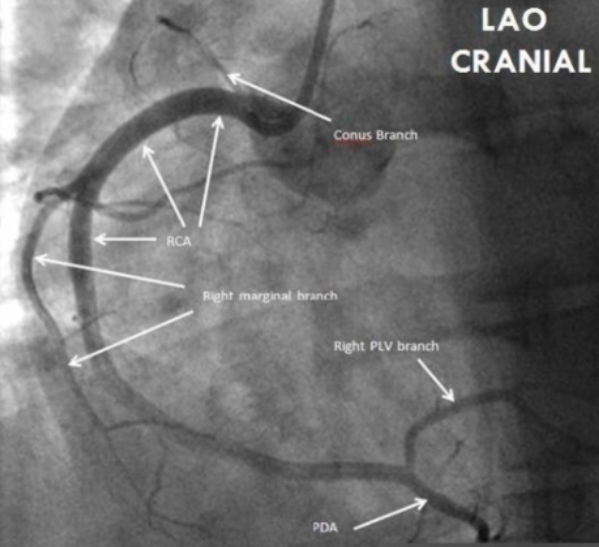

Where is the right coronary artery (RCA), and what part of the heart does it supply?

1

Right atrium and ventricle, inferior LV wall, AV/SA nodes, 1/3 of septum

Which coronary artery is seen with a CT angiogram in the LAO cranial view?

A

RCA and branching into PDA